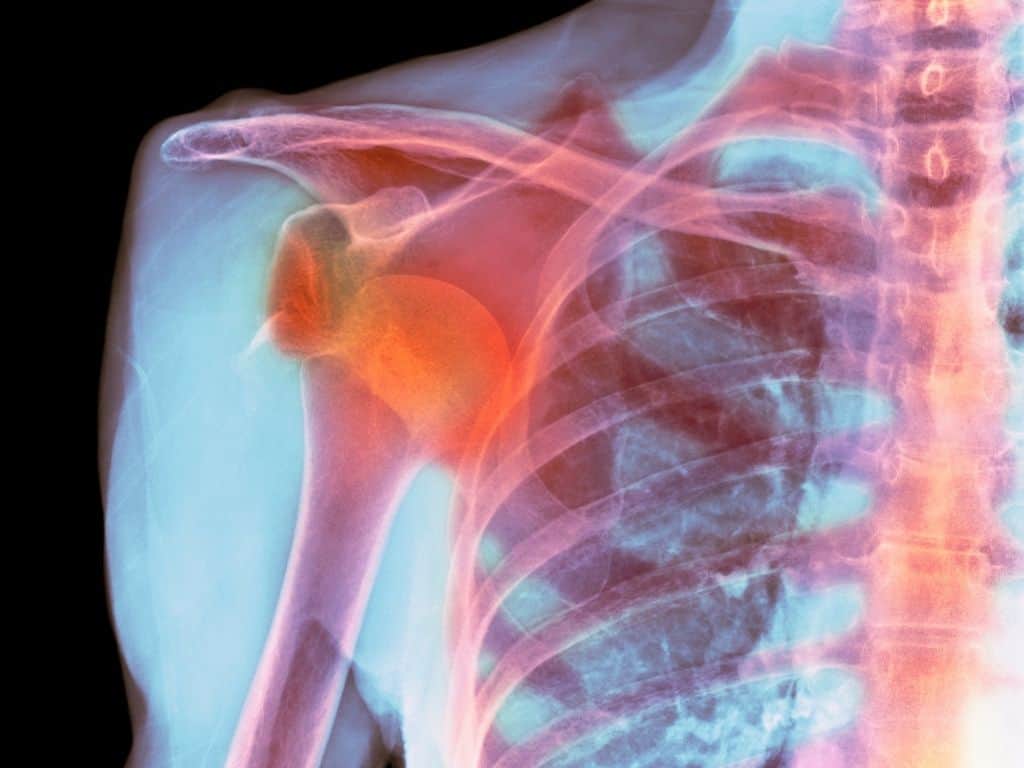

Esse termo se refere ao deslocamento do osso do braço, chamado de úmero, em relação à cavidade glenoidal da escápula.

O ombro é constituído por três articulações e três ossos distintos, eles são: o osso do braço, chamado de úmero, o omoplata e a clavícula.

A luxação no ombro ocorre quando as duas superfícies da articulação do ombro (ou articulação glenoumeral, ligada à cabeça do úmero e a cavidade glenoidea) sofrem uma perda de contato e congruência.

Para se obter um diagnóstico preciso é necessário fazer exames físicos e outros exames auxiliares, como a radiografia, com muita cautela.

Em alguns casos, mais agravados, é preciso fazer exames mais específicos, como a tomografia axial computadorizada e a ressonância magnética.